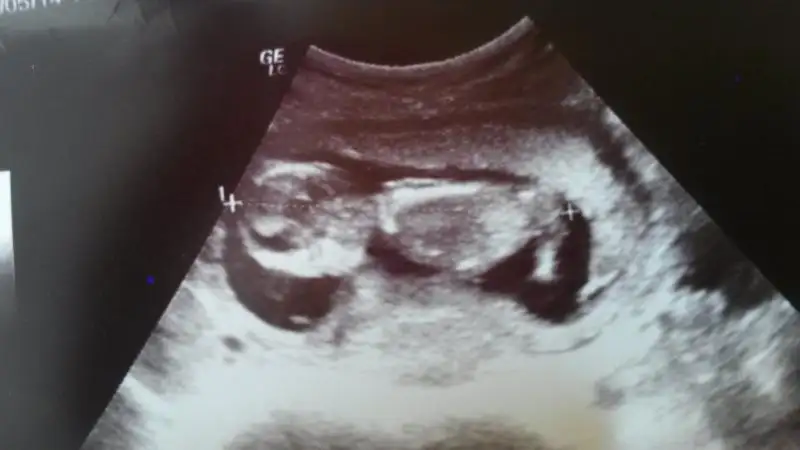

kızlar banada bir yorum yapabilirmisiniz?

Bence seninki kız canım, çünkü internetteki bütün kız resimlerine benziyor seninki çok belirgin :) Allah gönlüne göre ve sağlıklısını versin :)